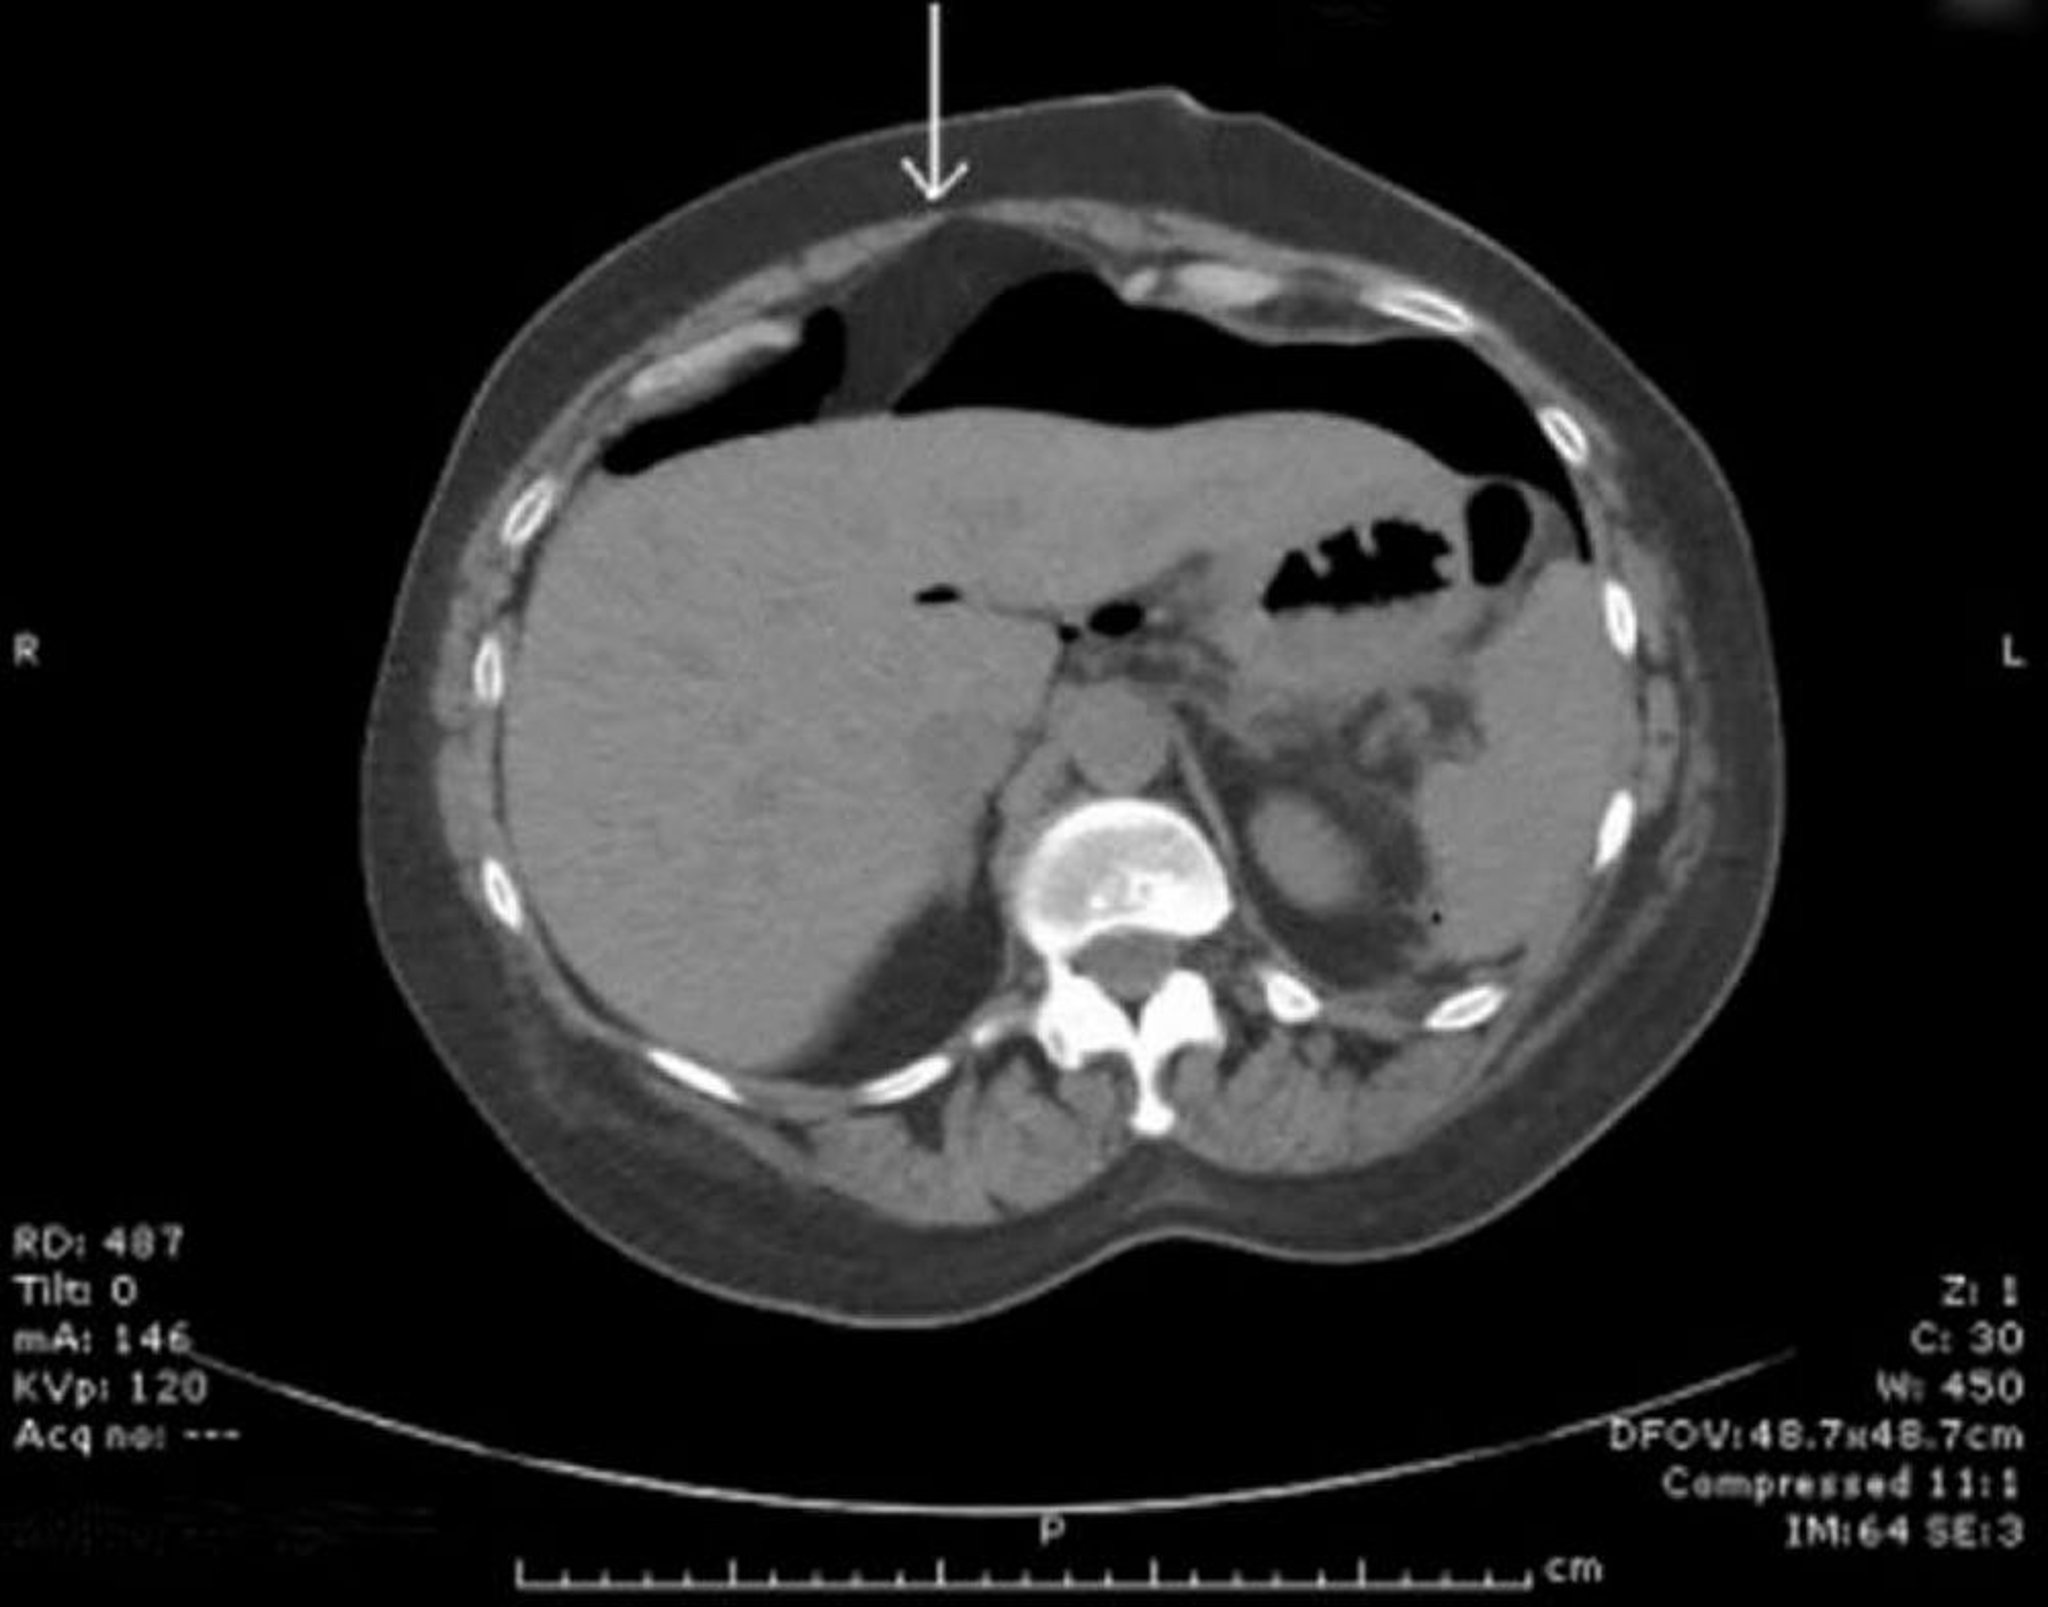

CT có khí tự do trong phúc mạc

Khí tự do được nhìn thấy trước gan. Mũi tên chỉ vào dây chằng liềm.

Hình ảnh do bác sĩ Parswa Ansari cung cấp